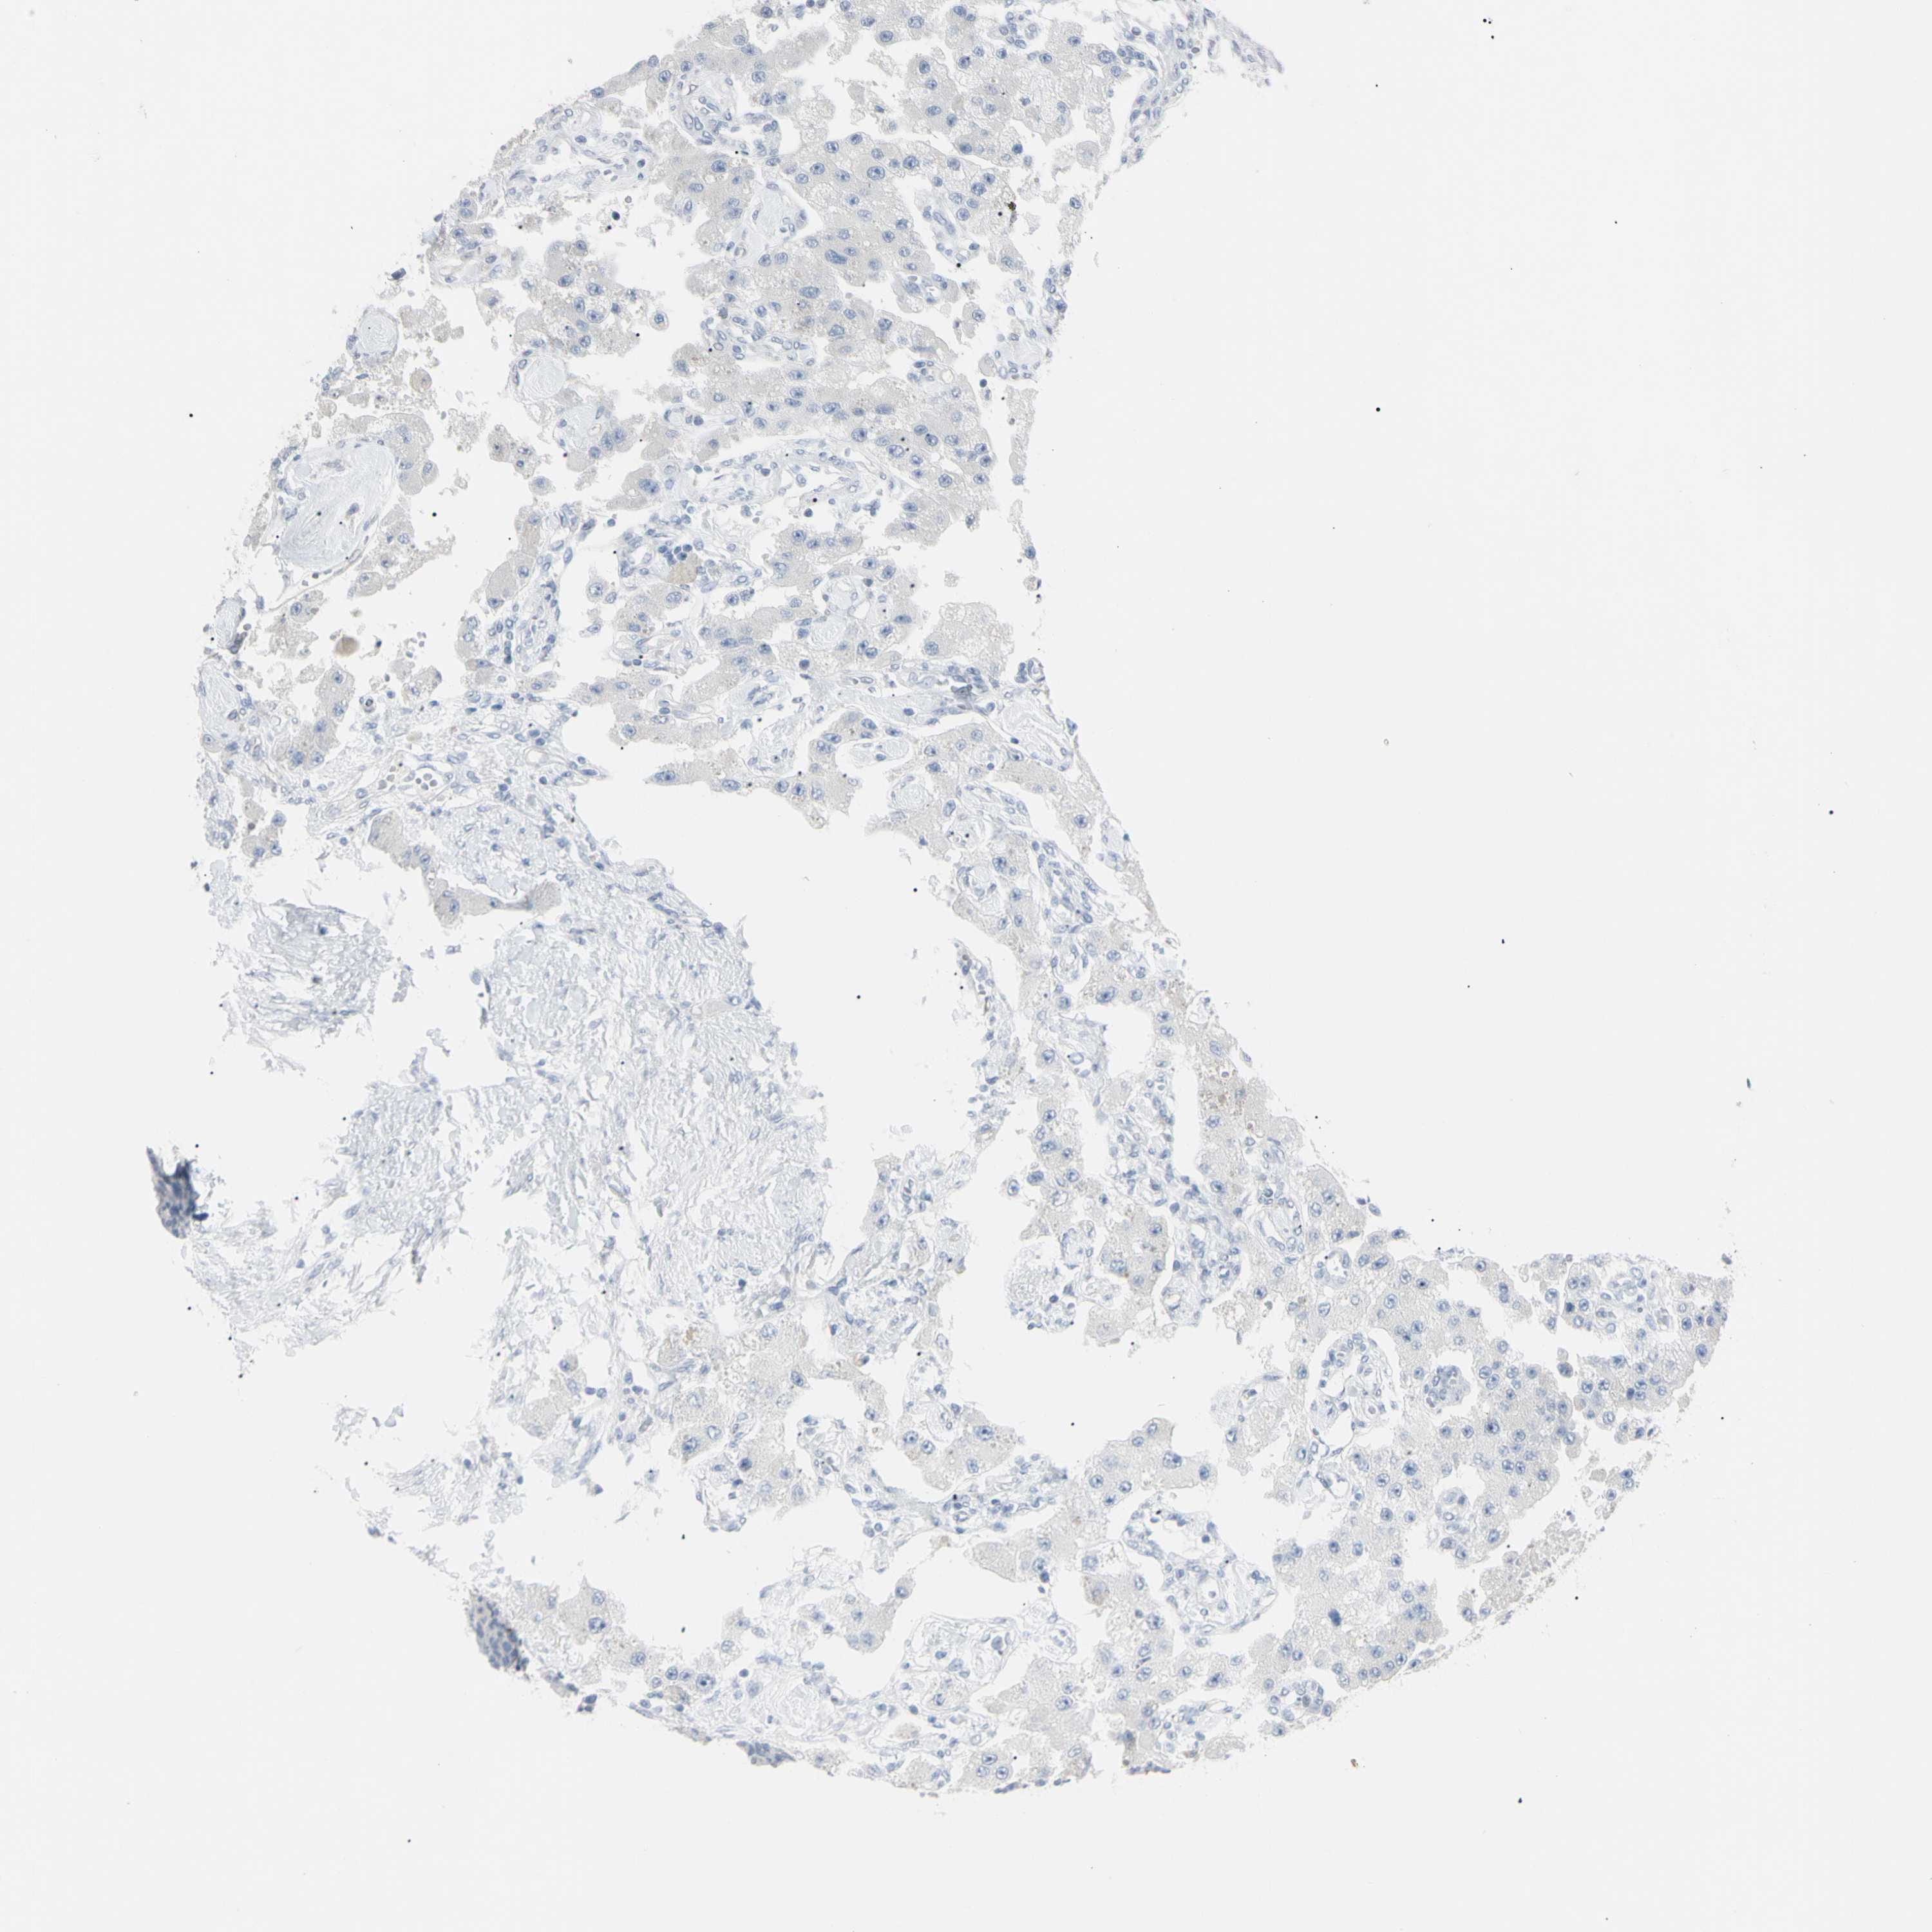

CARCINOID - Protein expressioni

A mouse-over function shows sample information and annotation data. Click on an image to view it in a full screen mode. Samples can be filtered based on level of antibody staining by selecting one or several of the following categories: high, medium, low and not detected. The assay and annotation is described here.

Antibody staining in the annotated cell types in the current human tissue is reported as not detected, low, medium, or high, based on conventional immunohistochemistry profiling in selected tissues. This score is based on the combination of the staining intensity and fraction of stained cells.

Each image is clickable and will lead to virtual microscopy that enables deeper exploration of all samples and also displays staining intensity scores, fraction scores and subcellular localization as well as patient and tissue information for each sample.

Antibody CAB002661

Carcinoid, malignant, NOS